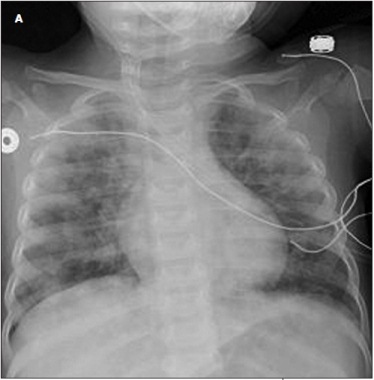

Avind Rampersad, MD; Avind Hamad, MD; Pierre Vauthy, MD

<DIV id=article-content-body> <P><IMG style="MARGIN: 5px; FLOAT: left" alt="heiner syndrome" src="/sites/default/files/transfer/0912cfpPCheiner1_thumb.jpg"...